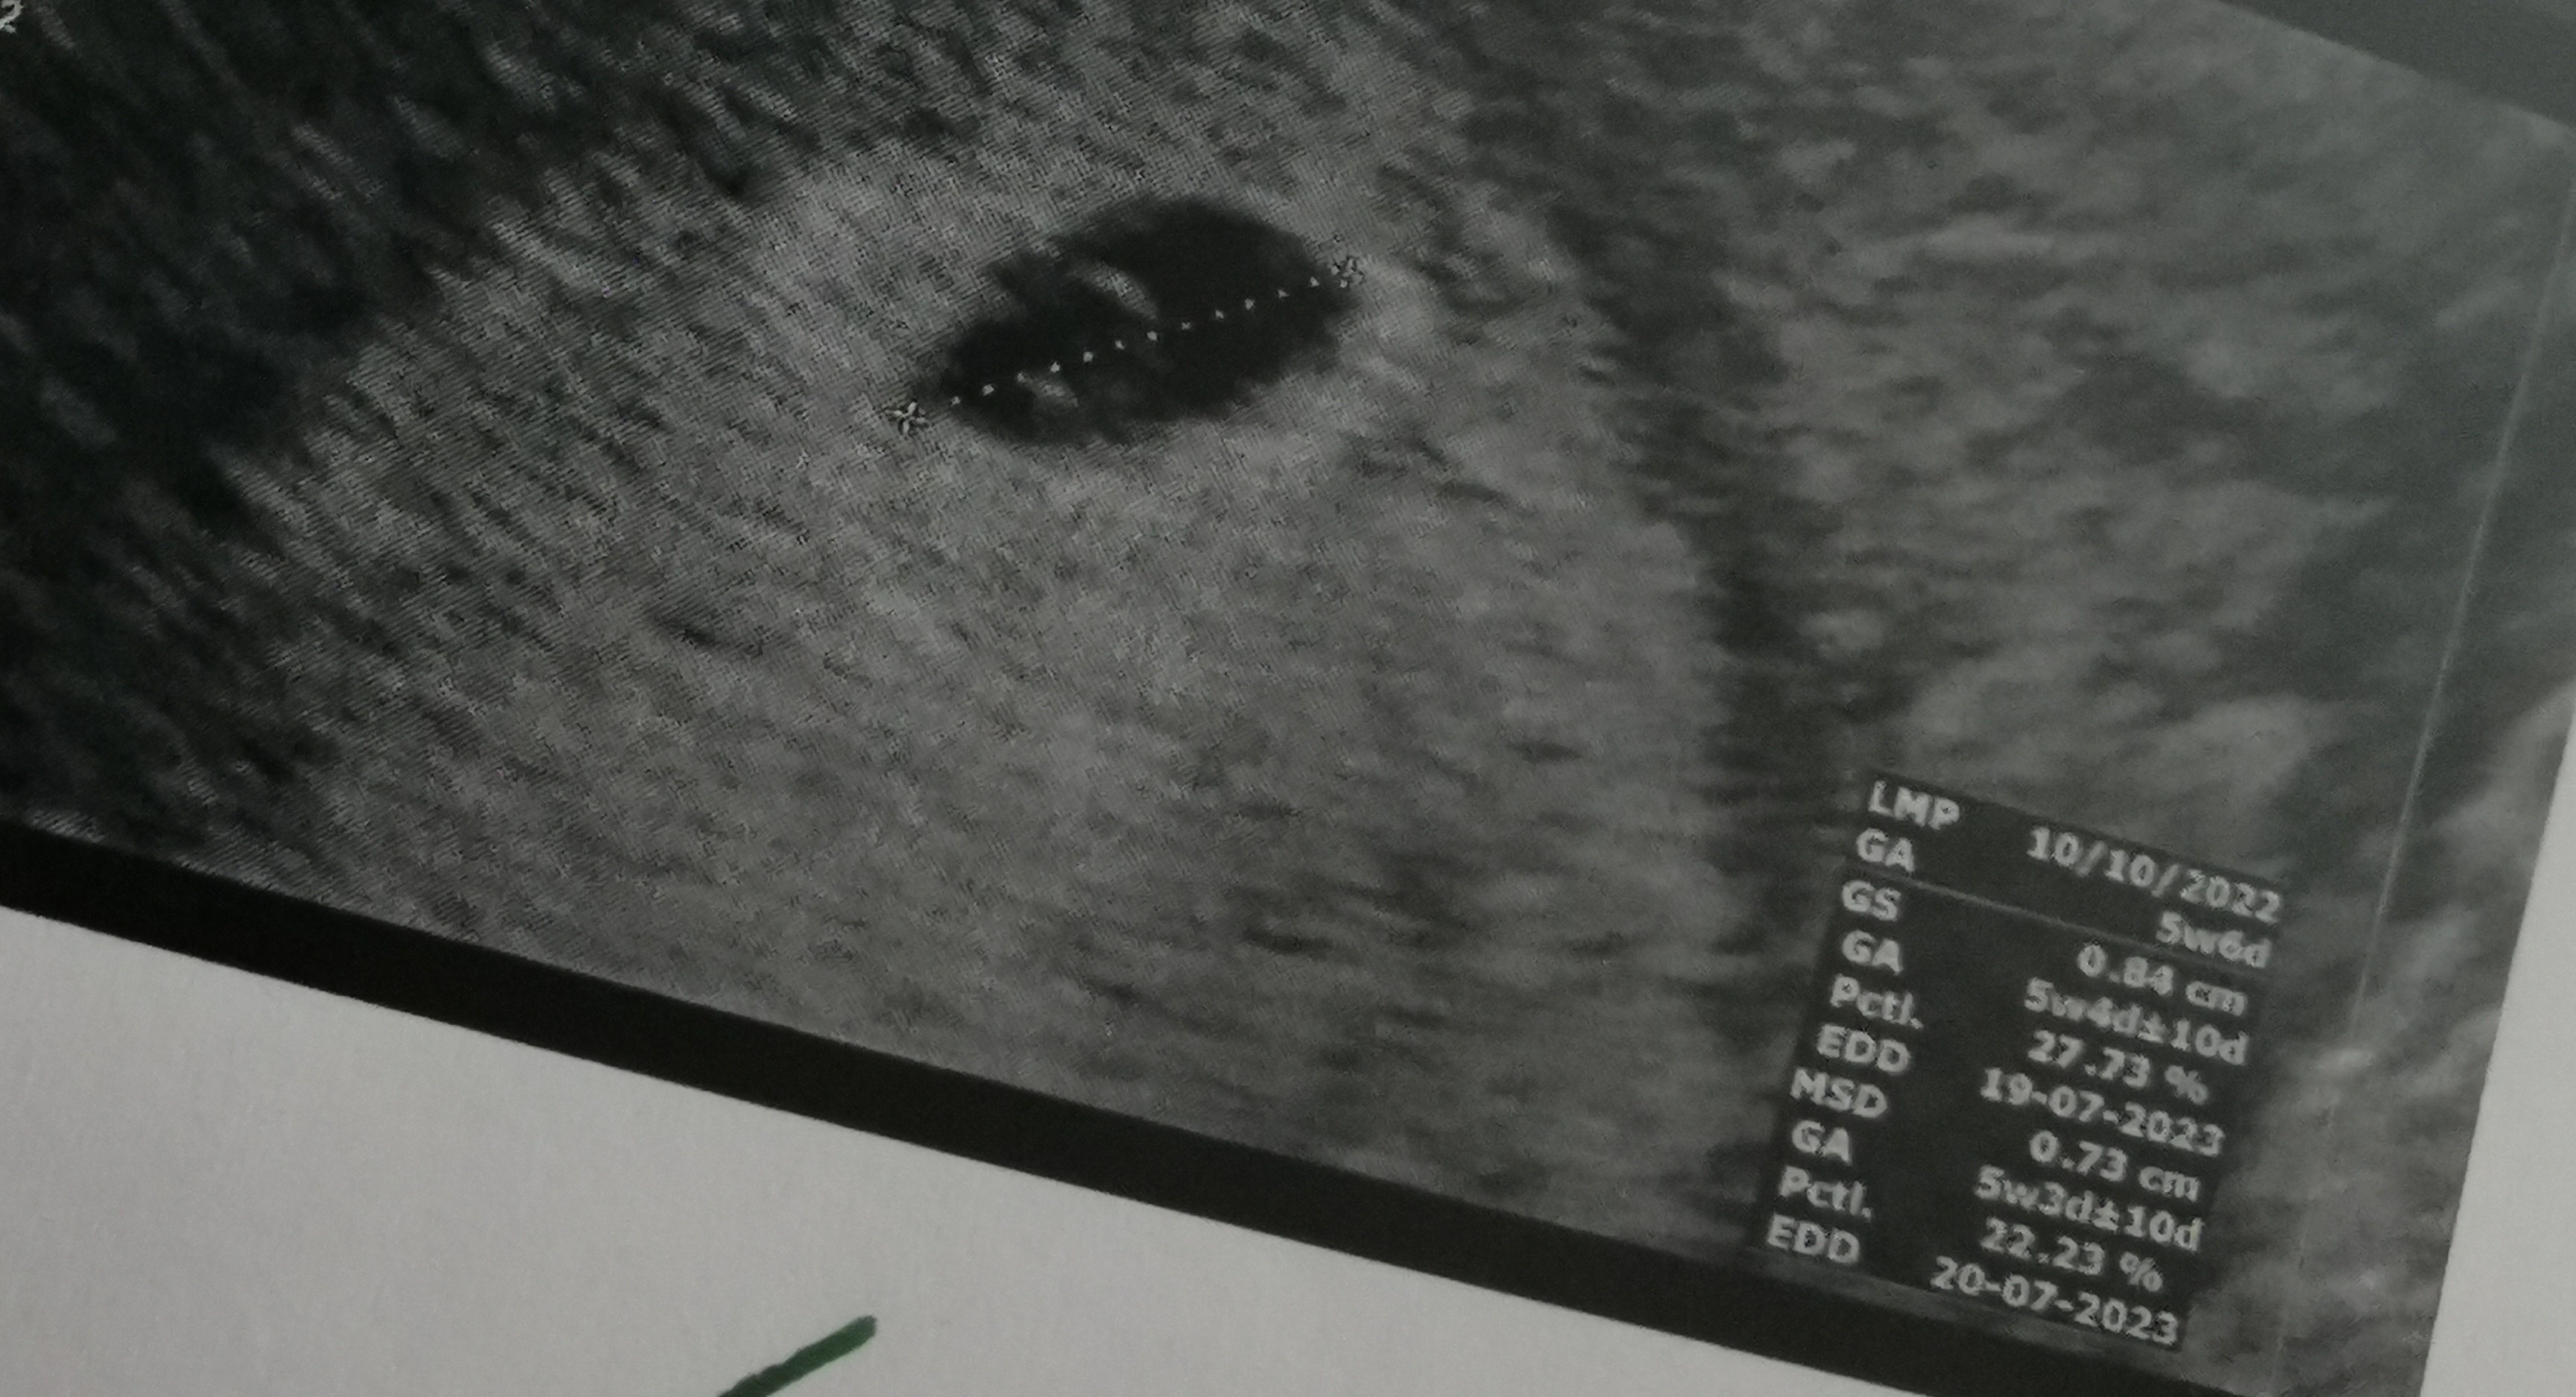

U mnie 5+3 (lub 5+4) usg wyglądalo tak przy becie ponad 2000: